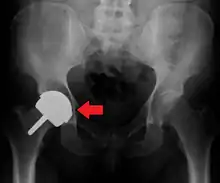

Dislocation

Dislocated artificial hip

Liner wear, particularly when over 2 mm, increases the risk of dislocation.[6] Liner creep, on the other hand, is normal remoulding.[7]

Dislocation (the ball coming out of the socket) is the most common complication. The most common causes vary by the duration since the surgery.